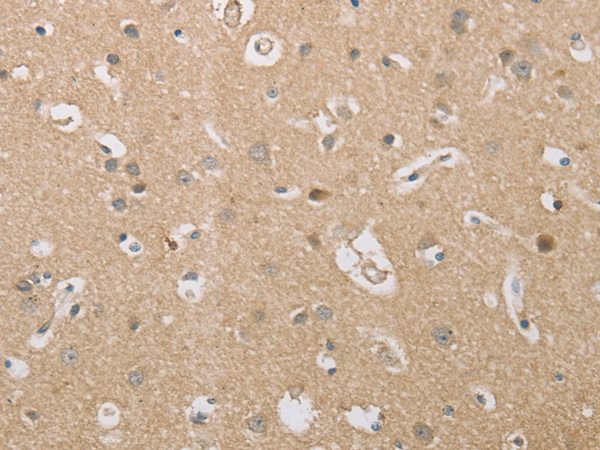

分类: 科研抗体货号: P11279别名: NEF5, NF-66, TXBP-1应用: WB,IHC反应种属: Human, Mouse